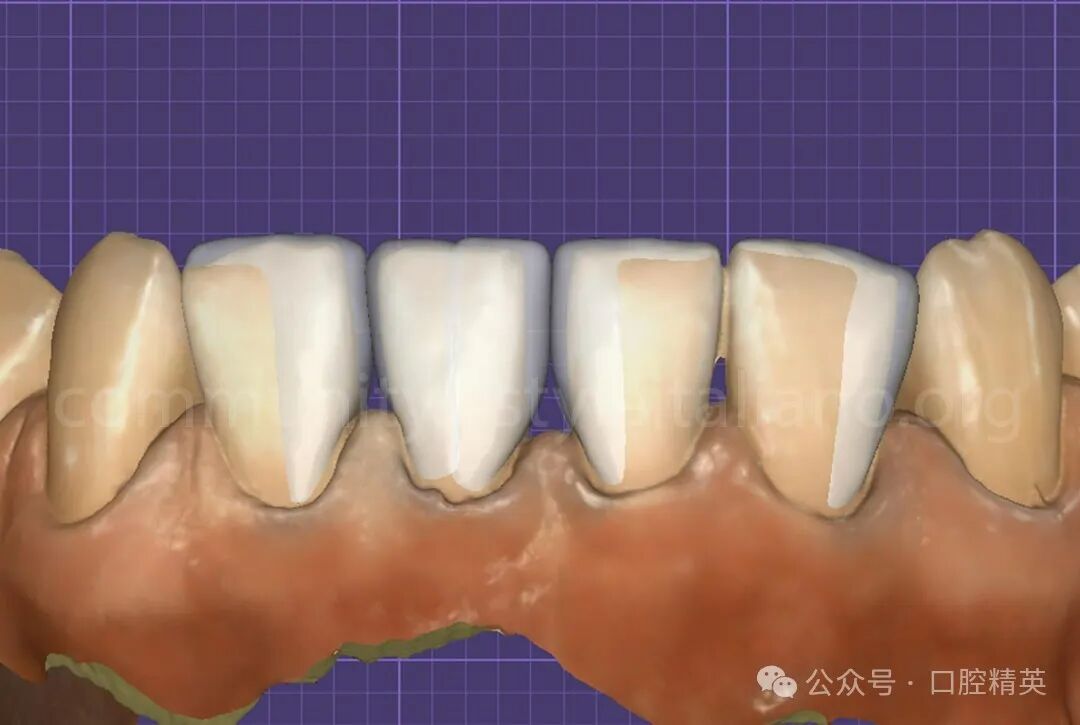

图2 设计采用Exocad软件设计,保持最小允许厚度。两个独立的贴面被数字化建模-每个中切牙一个。